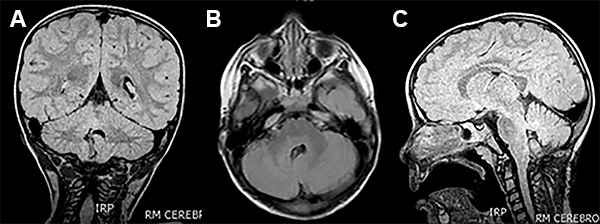

La RMN mostró una lesión tumoral en el hemisferio cerebelos derecho en intimo contacto con los pedúnculos cerebelos medio y superior derecho (fig. 6).

Figura 6: Caso 3. Imágenes prequirúrgicas.

Paciente de 4 años de edad sin antecedentes perinatológicos de importancia que a los 3 años de edad comienza con movimientos clónicos de comisura labial a derecha que fueron asumidos como normales. Ocho meses después del inicio de los movimientos clónicas de la comisura labial, la niña presenta fijeza de la mirada con posterior desviación de la comisura labial a derecha y posteriores movimientos tónicos clónicos generalizados que se repitieron varias veces (fig. 7).

Figura 7: Caso 4: Imágenes preoperatorias